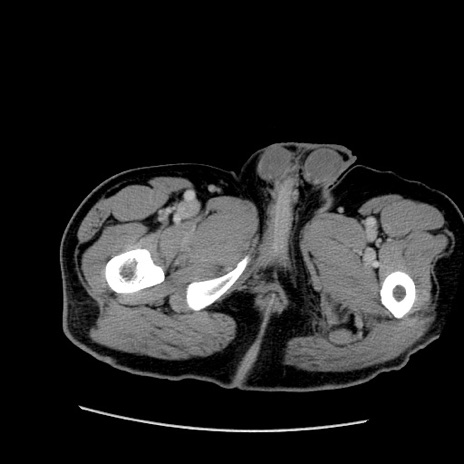

症例22(横断像)

【症例】50歳代男性

【主訴】腹痛

【現病歴】AVMからの被殻出血のため回復期リハ病棟入院中。 本日午後3時頃急に下腹部痛が出現した。

【既往歴】AVM、被殻出血、虫垂炎、高血圧

【身体所見】意識晴明、左半身不全麻痺、会話の理解は良好、36.5°C、腹部:膨隆、全体に板状硬、下腹部正中に圧痛点あり、反跳痛-、筋性防御不明、右下腹部にope scar

【データ】WBC 9400、CRP 0.06